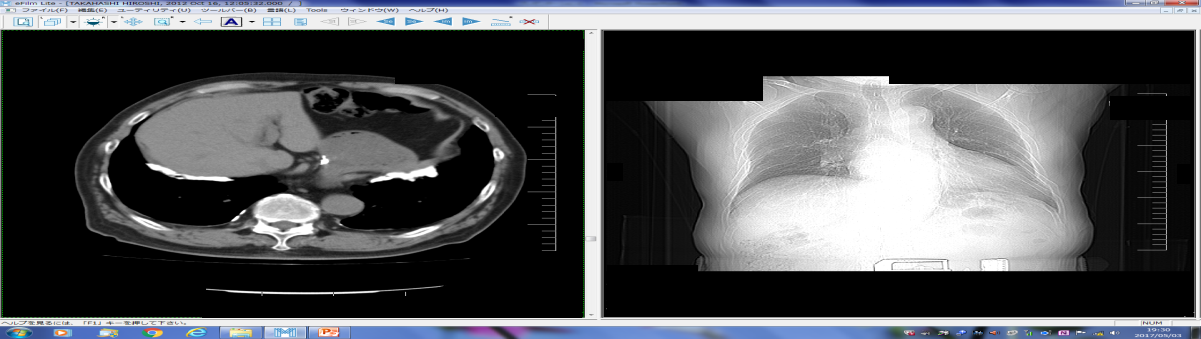

(3)造船労働者の胸部XP/CT写真の胸膜プラーク所見

私たちは1989年から2016年時まで退職した造船労働者の健康管理を27年間行った5)。退職後長年観察した例は稀で胸膜プラークの変化に着目した。15年間以上毎年胸部X線写真を撮影、胸部CT写真を10年間以上で3回以上撮影した「石綿肺管理2以上+続発性気管支炎」で労災認定された23名を対象とした(初回管理2以上17名、中間時管理2以上6名)。医師3名が独立して初回、観察中間時、最新回の胸部XPと胸部CT写真を読影、医師間の所見の異なる写真は再意見を求め再意見の各自読影結果を最終結果とした。対象は全員男性、現在・死亡時平均年齢は87歳(80~96歳)、初診時平均年齢は64歳(58~72歳)従事年数は平均35.3(17~41)年、職種は溶接7名、機関6名、ボイラー4名他6名で、非喫煙3名・前喫煙20名・現喫煙0名で平均喫煙係数611(220~1520)だった。2016年現在生存14名、死亡9名(平均年齢86.1<80~90>歳)、胸部X線写真観察期間は平均21.5(15~26)年で医師の読影所見は22名で一致した5)

1. 初回~最新回XPとCT共に胸膜プラーク有9名(39.1%)平均年齢65.1(62~72)歳【写真1】

3. 初回XP胸膜プラーク無・CT有7名(30.4%)平均年齢73.4(66~80)歳【写真2】

5. 初回XP/CT胸膜プラーク無・最新回XP無・CT有は3名で【写真3】胸膜プラークの確認時年齢は69・77・80歳、80歳時点の胸部CTはプラーク検出に有意義だった。

7. 初回~最新回CTで胸膜プラーク無4名中3名永眠(80~84歳)し85歳1名が生存中。

9. 23名中肺癌が3名に発症し発症時年齢79、81、88才で、円形無気肺を 2名に認めた5)。

【写真1】胸膜プラークの胸部X線写真 典型的な経過5)

【写真2】初回XP胸膜プラーク(-)初回CT胸膜プラーク(+)

【写真3】初回CT胸膜プラーク(-)最新回CT(+)

胸部X線写真で胸膜プラークのある場合、胸膜プラークは経年的に厚く大きくなり徐々に石灰化した【写真1】。胸膜プラークはCTで66~80歳で初めて認められ、70台,80才の胸部CT写真撮影の必要性が認められた【写真3】。高濃度石綿ばく露をうけた23名中4名に80台でも胸部CTで胸膜プラークのない群が確認された。肺がんによる死亡が3名に認められ、胸膜プラーク有は1名で2名はXP・CT共に最後までプラークなしだった。職業性石綿ばく露を受けた集団は、退職から永眠までの期間の健診体制を必要とし、胸部X線CT写真を併用し観察する意義が再確認された5)